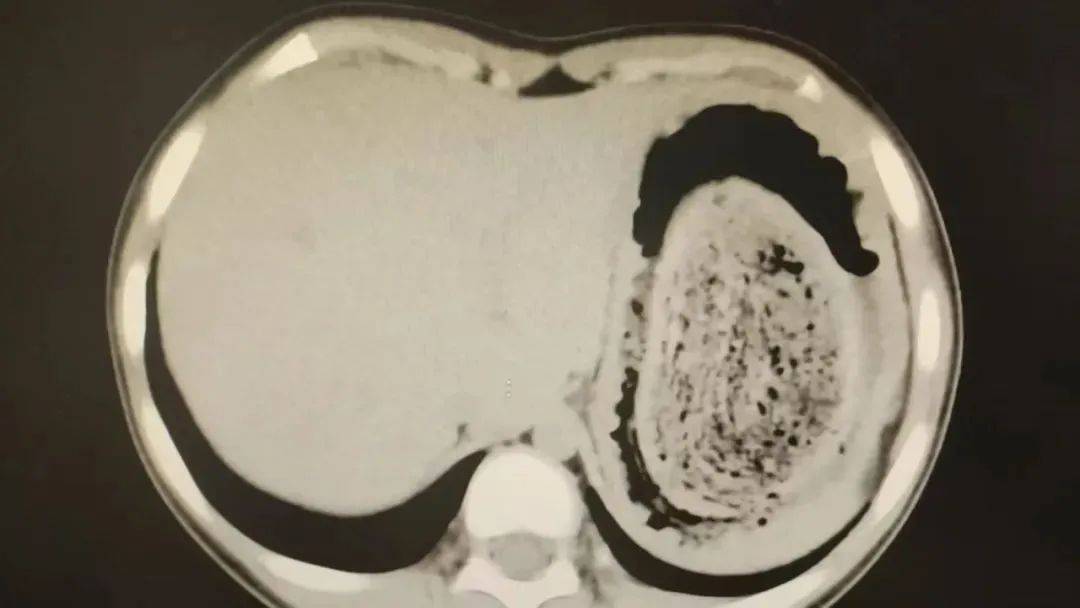

结果出来时,医生都惊呆了:小可的胃里,塞满了成团的头发,几乎占了胃容量的四分之三。大量不能消化的物质,在胃酸的作用下发生变性,并与食物及其他物质结合形成团块,慢慢变成坚硬的“胃石”。

为了避免用手术方式去除头发团, 陈攸涛先让小可喝可乐软化“胃石”,再通过胃镜辅助取出头发,整个过程花了十几个小时,清理出的头发装了 两大盆。